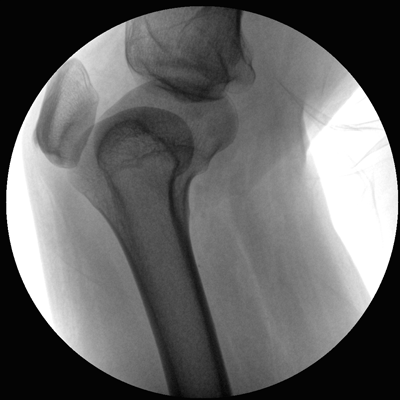

小巧輕便 超凡靈動 PLX116

●一體化機(jī)架設(shè)計,占地空間小,移動靈活

●一人獨立操作,即可完成C形臂的移動與曝光

●全數(shù)字化百萬像素影像系統(tǒng),圖像清晰

●多種工作模式任意選擇,滿足多種臨床需求